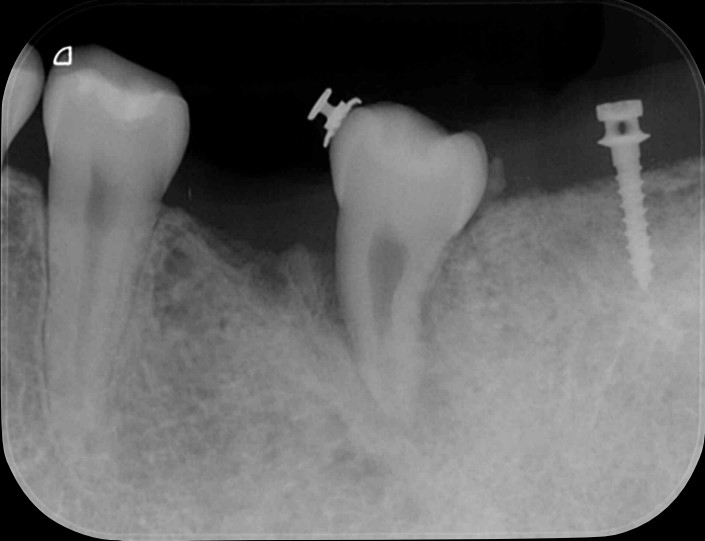

歯の移植

Before

After

初診時

プチ矯正

神経生きたまま